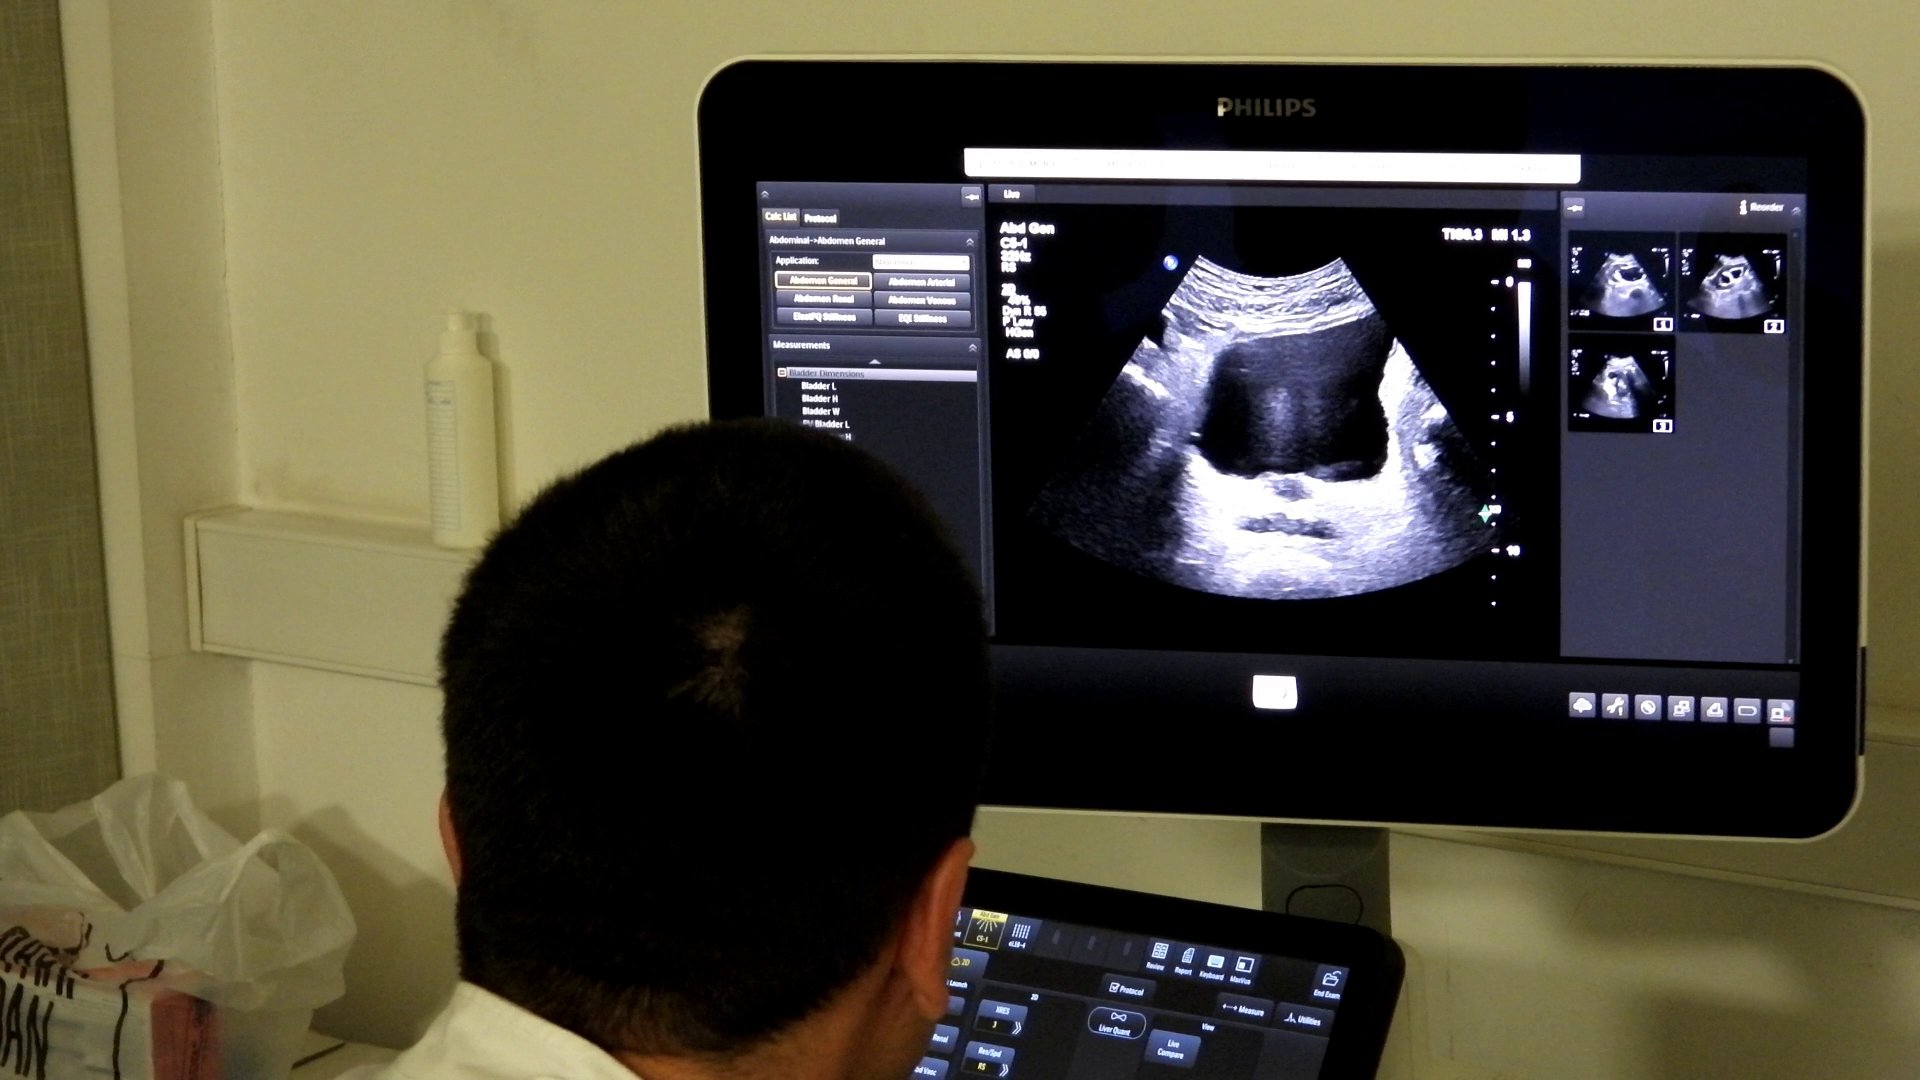

Dr. spec. radiolog Aida Vehabović iz Kantonalne bolnice Zenica (KBZ) je pojasnila je strukturu edukacije i značaj praktičnog rada.

– Prvi napredni kurs Ultrazvučne škole abdomena, je dio kontinuirane edukacije koja se sastoji od bazičnog i naprednog kursa. Devet ljekara steklo je certifikate za samostalni rad u ultrazvučnoj dijagnostici abdomena. Dio vizije kontinuirane edukacije jeste jačanje zdravstvenog sistema u smislu dostupnosti ove dijagnostičke metode pacijentima u njihovim lokalnim zdravstvenim ustanovama, rekla je dr. Vehabović.

– Polaznici su tokom kursa imali priliku raditi sa velikim brojem pacijenata različitih kliničkih stanja i patologija, uključujući i rijetke, te su stekli stručnu kompetenciju za samostalan rad na što smo posebno ponosni, rekla je dr. Vehabović.